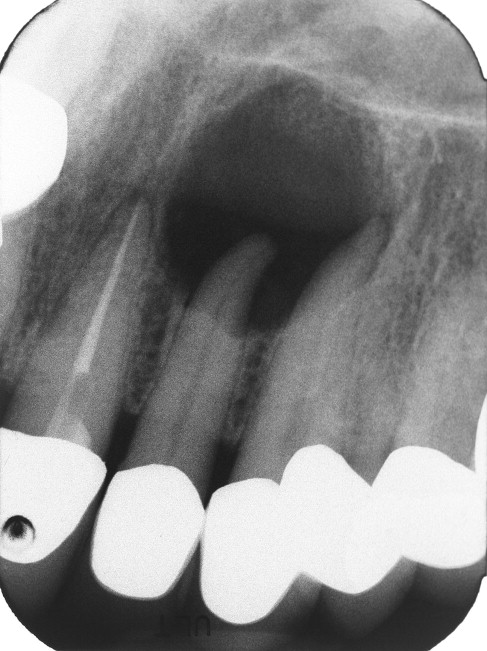

2.2. Hình ảnh X. quang

– Hình ảnh X.quang điển hình của nang chân răng là một vùng thấu quang, hình tròn hoặc ô van có đường ranh giới rõ ràng bao quanh cuống hay ở về một bên cuống của một răng chết tuỷ hoặc ở vùng tương ứng cuống của một răng hỏng tủy đã được nhổ đi. Thường là nang một buồng. Với những nang lớn có thể có hình ảnh X.quang nhiều buồng.

– Đọc phim cần chú ý: Vị trí nang, đường kính, ranh giới, 1 hay nhiều ổ, chân răng trong nang, liên quan với các bộ phận giải phẫu như xoang hàm, ống thần kinh răng dưới.